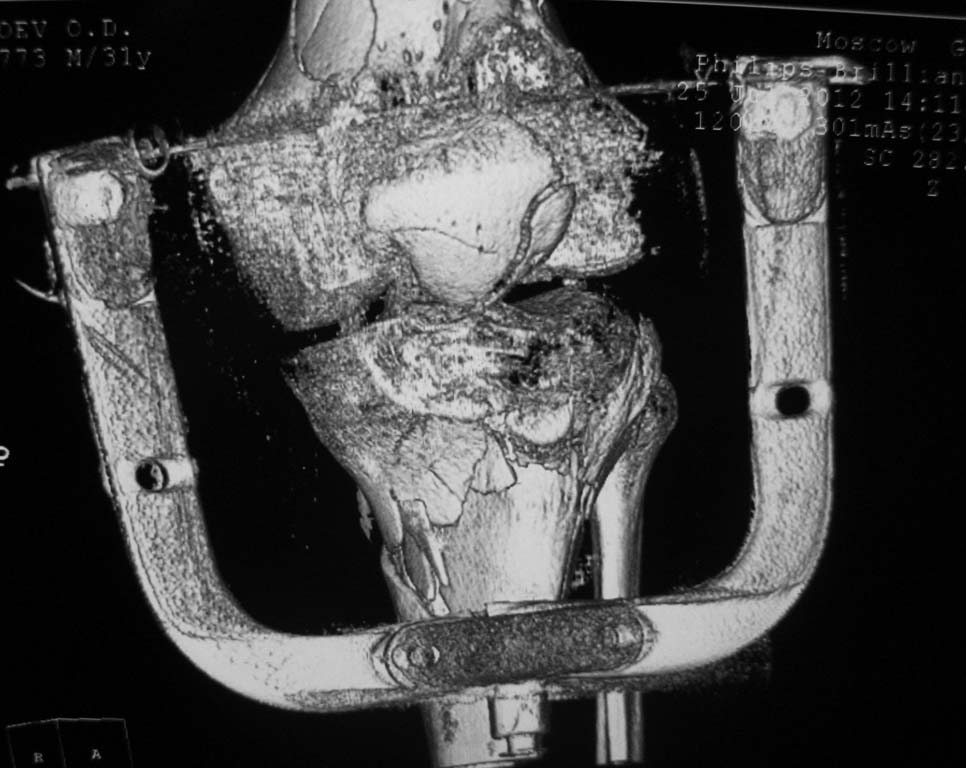

Нужен совет. Открытый перелом в\3 диафиза с оскольчатым переломом дистального метаэпифиза бедра. Закрытый оскольчатый внутрисуставной перелом проксимального отдела большеберцовой кости той же конечности.При поступлении ПХО ран, скелетное вытяжение. Рана зажила первичным натяжением. Осложнилось правосторонней пневмонией. Предстоит выбрать тактику оперативного лечения и камими имплатнатами.По нашему мнению случай нестандартный, требуется обсуждение коллег.

Добрый вечер. На проксимальное бедро длинную гамму. Внутрисуставные переломы только открыто. На бедренную кость опорную мыщелковую пластину LCP. На голень две Г образные LCP с латеральной и медиальной стороны. Возможна менискэктомия. Активные движения в коленном суставе в раннем п/о периоде. Оперировать желательно на ортопедической приставке.

Спасибо большое за совет, мы выбрали именно эту тактику. Диафиз бедра, учитывая то, что линия перелома идет до малого вертела, зафиксировали длинной PFNA, мыщелки бедра собирали на LISS. Вторым этапом большеберцовую кость проксимальной латеральной пластиной, правда только одной. Голень получилась не идеально, имеется варусный угол. Все имплантаты Synthes. Снимки с iPAD не получается скинуть. Если не заленюсь, дома скину с компа.